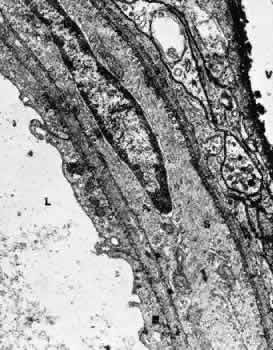

Retinal Arteries and Arterioles The retinal arteries are branches of the superior and inferior papillary arteries. Each papillary artery typically divides again on the surface of the optic disc to form temporal and nasal branches. The anatomical division of the retinal arteries into superior and inferior halves is usually maintained throughout the retina because vessels normally rarely cross the horizontal raphe. The major branch arteries are about 120 μm in diameter and course within the nerve fiber layer and ganglion cell layer of the retina. They are smaller in diameter and straighter in course than their accompanying draining veins. Subsequent division of the arteries results in a decrease in the caliber of the vessel. The branching is of two types: dichotomous and side-arm. Trifur-cations are extremely rare. Dichotomous branches involve two similar-sized trunks splitting from a larger trunk. Smaller vessels arising from dichotomous branches course toward the periphery of the retina, becoming arterioles that supply the retina anterior to the equator. Side-arm branches are small precapillary arterioles branching from a larger vessel to supply blood to the local capillary system. In the posterior retina, the fine arterioles that arise by side-arm branching leave the main arteries and enter the inner plexiform and ganglion cell layers. Only capillaries are found as deep as the inner nuclear layer, however. The blood column within retinal arterioles is visible with a direct ophthalmoscope down to the third-order branches. Normally, the walls of the vessels themselves are transparent to direct observation; it is the blood column that makes the vessels visible on ophthalmoscopy. The intima of the retinal arteries contains a single layer of endothelial cells surrounded by a basement membrane. Collagen fibrils may be seen in the basement membrane. Elastic fibrils are not present, and there is no internal elastic membrane. The media of the major vessels near the disc contains five to seven layers of circularly arranged smooth muscle cells. These cells contain well-developed myofilaments and dense bodies and are surrounded by a thick and often lamellated basement membrane containing collagen fibers. Collagen types 1, 2, 4, and 5, laminin, heparin sulfate proteoglycan core protein, and fibronectin all have been identified as components of the basement membrane.12 The basement membrane surrounding the innermost layer of the smooth muscle cells is continuous with the basement membrane surrounding the endothelial cells. Some areas exhibit a thinning of this membrane, and in these areas the membranes of the endothelial cell and smooth muscle cell are closely apposed. The basement membrane surrounding the outermost layers of smooth muscle cells contains increasing amounts of collagen and tends to become vacuolated and to accumulate debris with aging. As the major retinal arteries branch and approach the equator of the eye, the media becomes less well developed and contains approximately two layers of smooth muscle cells. At this point and further peripherally, the retinal vessels should be referred to as arterioles. The adventitia consists of collagenous connective tissue that is continuous with the basement membrane surrounding the outer layers of smooth muscle cells of the media. A smooth muscle cell may occasionally be displaced into the adventitia. Glial cells are in direct contact with the adventitia. No nerve fibers have been found in the media or adventitia of human retinal arteries or arterioles.13 Although the ophthalmic artery contains sympathetic nerve fiber endings and is therefore under control of the autonomic nervous system, there is apparently no central regulation of the blood flow in the retina itself. Evidence implies that some species may have autonomic innervation of the preretinal blood vessels, however.14 Retinal arterioles are similar to the arteries except that the lumen is small (8 to 15 μm in diameter), the media contains one or two layers of circularly or obliquely arranged smooth muscle cells, and the adventitia is poorly developed and consists of the outermost layer of basement membrane surrounding the smooth muscle cells and small amounts of collagen fibrils (Fig. 4).15